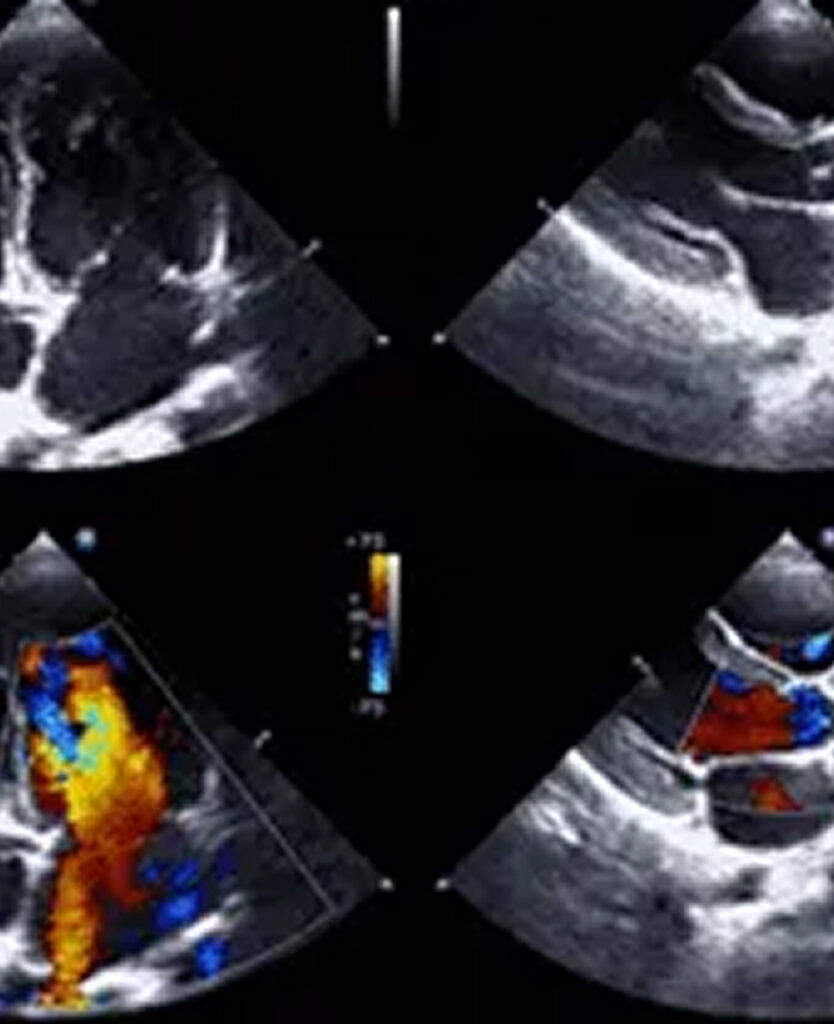

Our services

At Carrington Cardiology Centre, we offer a full spectrum of investigative and treatment services to keep your heart in top shape. From detailed diagnostic tests to personalised treatment plans, our friendly team is committed to providing exceptional care tailored to your needs. Let us help you achieve and maintain optimal heart health.